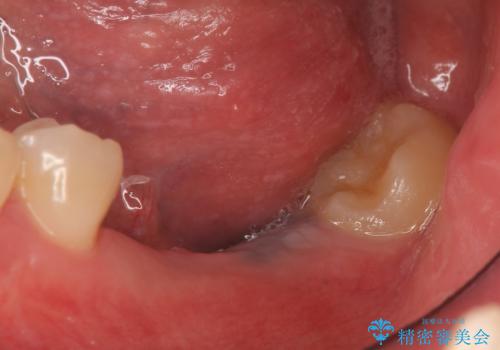

- 数年前に左下の奥歯を2本失ってから物が咬めないため何とかして欲しいと当院にいらっしゃった方の症例です。

左下にインプラント(ストローマン)を2本埋入し、オールセラミッククラウンによる補綴を行いました。